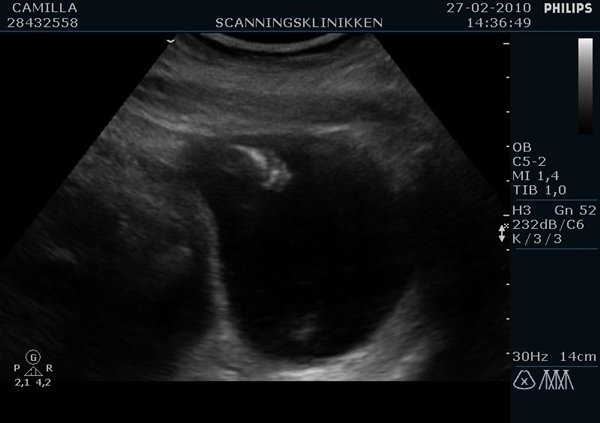

Ville lige ligge lidt billeder ind af min lille pige (Emilie?)  fra kønsscanningen igår

Billedet af hendes ædlere dele beviser 2stk skamlæber, (de to prikker)

Jordemoderen scannede mig fra alle leder og kanter og der var hverken tap eller pung at finde